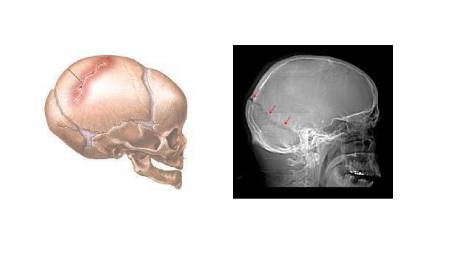

Según el neurocirujano del Hospital La Luz, "podríamos decir que hay traumatismos craneoencefálicos cerrados, donde no hay heridas en el cuero cabelludo y abiertas, donde hay heridas en la piel del cráneo y fracturas de algún hueso craneal. "También podemos distinguir las que presentan pérdida de conciencia y las que no. Pero lo más importante es que ocurre en el cerebro".

Este especialista asegura que la mayoría de fracturas de cráneo van acompañadas de una lesión en el cerebro que puede ser grave o no. Según indica Villarejo, es Importante destacar que las fracturas de cráneo no requieren escayolas, ni férulas, ni inmovilización, pues cicatrizan solas en menos de 6 meses. El problema es que ocurre en el cerebro. Al principio puede haber un hematoma agudo intracraneal que requiere tratamiento quirúrgico para evacuarlo, o puede existir un edema cerebral (hinchazón del cerebro) que requiere una descompresión quirúrgica. "Pero puede ocurrir que el paciente se recupere de un traumatismo por la nieve o por un accidente de tráfico y al cabo de uno o dos meses desarrolle un hematoma subdural (entre la meninge y el cerebro), y que llamamos hematoma subdural crónico. "He tenido la ocasión de operar dos de estos hematomas producidos por golpes esquiando y que desarrollaron este tipo de hematomas, uno era un piloto de aviación de Iberia y el otro un alto ejecutivo. Los dos están muy bien actualmente", asevera el doctor Villarejo.